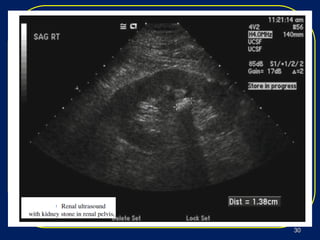

 Ultrasound is inferior to CT for visualization of stones,Ultrasound is inferior to CT for visualization of stones,

compared to spiral CT as the gold standard .compared to spiral CT as the gold standard .

 Ultrasound can only image the kidney and proximalUltrasound can only image the kidney and proximal

ureter and may miss distal stones.ureter and may miss distal stones.

 Although a suboptimal imaging modality forAlthough a suboptimal imaging modality for

nephrolithiasis, ultrasound does not use radiation andnephrolithiasis, ultrasound does not use radiation and

should be used in cases where radiation isshould be used in cases where radiation is

contraindicated, such as pregnant patients.contraindicated, such as pregnant patients.